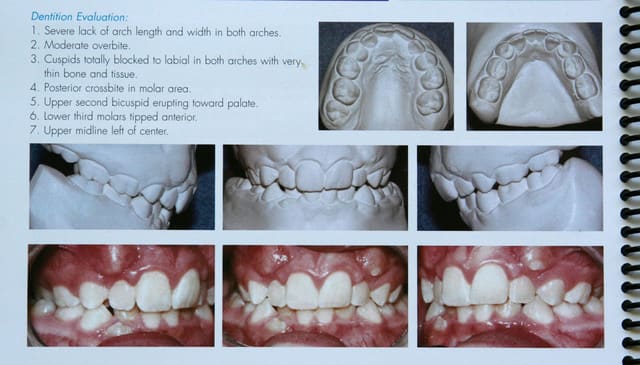

Ce cas, relativement facile à traiter en technique passive,

serait beaucoup plus difficile à traiter en technique bioprogressive.

Exemple du vieil adage :

Pourquoi faire simple quand on peut faire compliqué ?

@+ Bjc.

P.S. : je vous prépare plus difficile.

si je vous ai montré ce cas de D.D.M. c’est afin de vous prouver que les extractions sont de moins en moins nécessaires.

Si j’arrive à le faire, en n’étant ni prof, ni membre de sociétés réputées, c’est qu’avec les techniques actuelles, ce n’est pas très difficile

C’est à la portée de tout orthodontiste